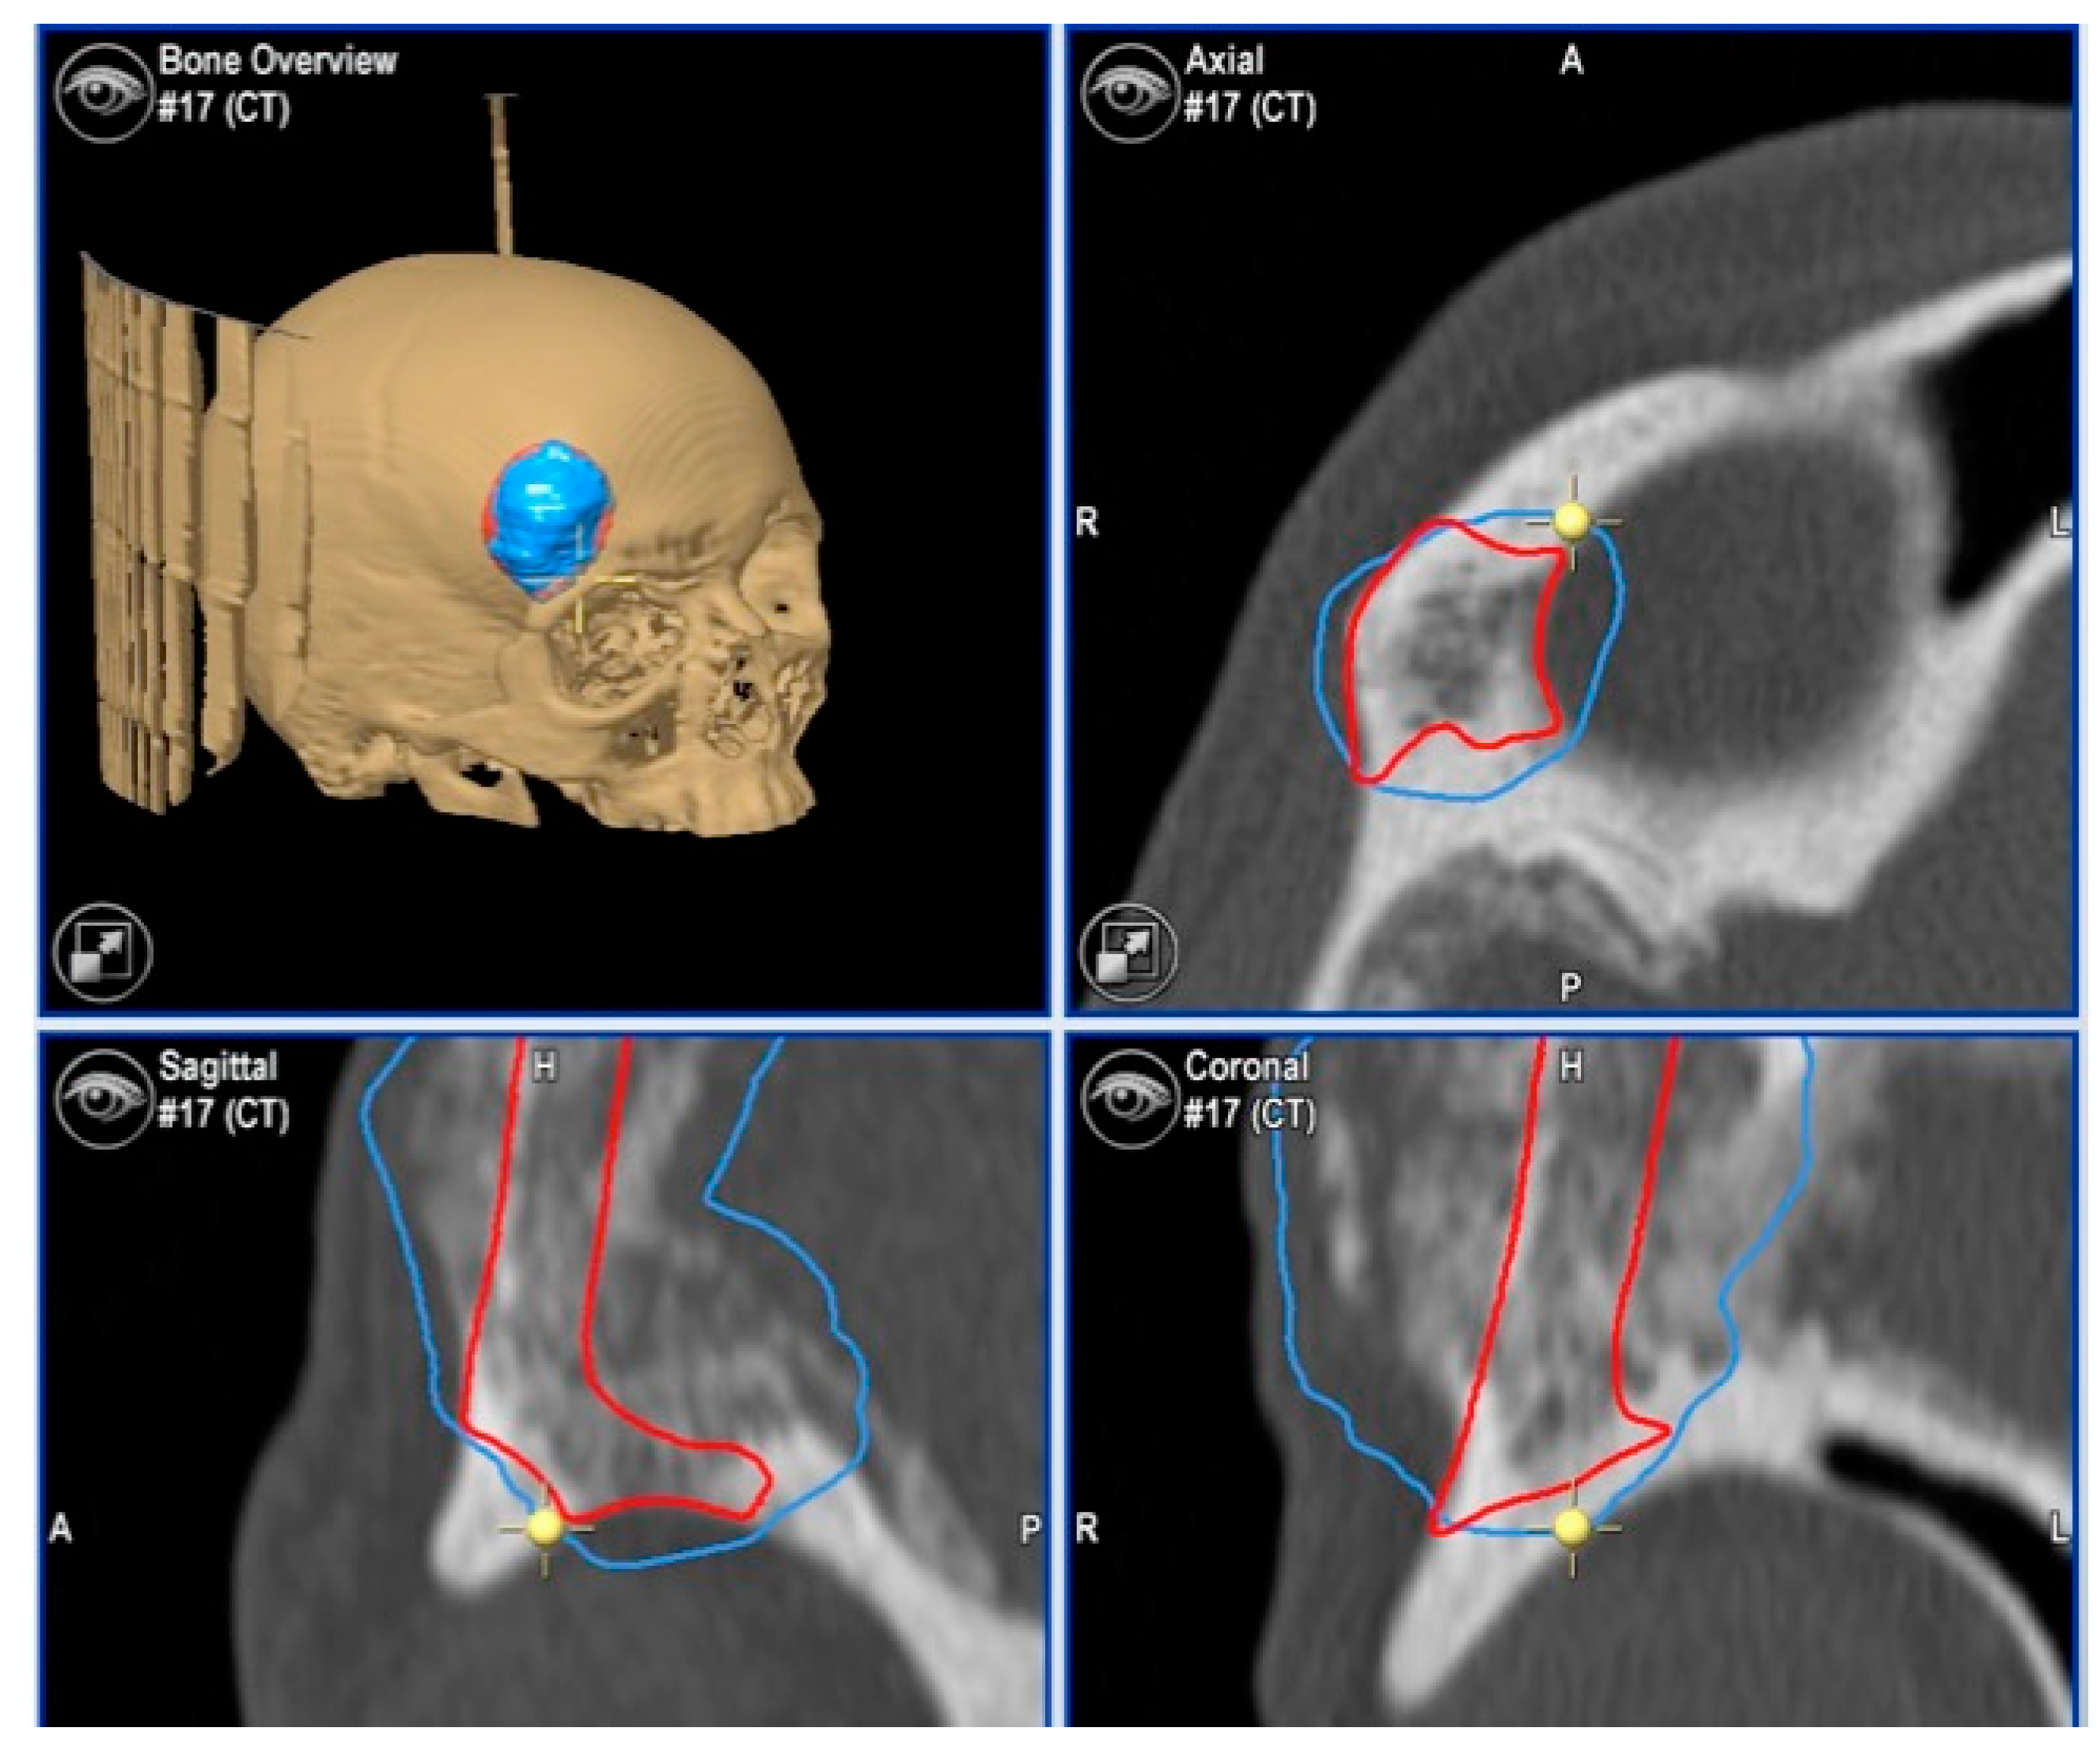

2.3.1. Virtual Surgical Plan

2.3.2. CAD-CAM Design of the PEEK Prosthesis

2.3.3. Surgical Navigation